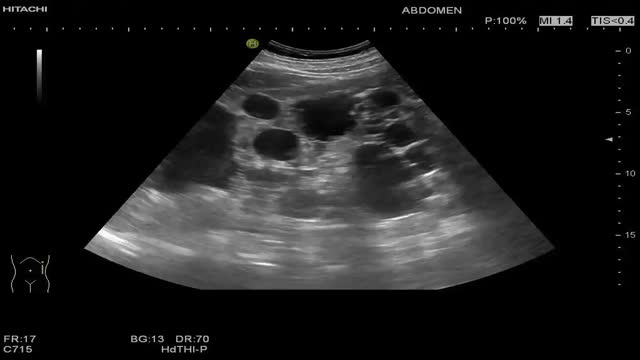

Poliquistosis renalLa poliquistosis renal es una enfermedad autosómica dominante que se caracteriza por la presencia de múltiples quistes simples en ambos riñones, asociado o no a quistes simples hepáticos (poliquistosis hepatorrenal). El crecimiento de estos quistes destruye el parénquima renal y puede generar enfermedad renal crónica. El diagnóstico precoz de esta patología es importante porque se consigue un seguimiento clínico más estricto, se cumplen los objetivos terapéuticos y se retrasa el avance de la enfermedad. La ecografía abdominal es la mejor técnica de imagen para el diagnóstico, el cribado de familiares y el seguimiento de pacientes. Los hallazgos ecográficos observados son múltiples lesiones quísticas, la mayoría simples, de tamaño muy variable que aumentan de forma importante el volumen renal total (VRT) que se ha visto una relación directa entre el VRT y la pérdida funcional del riñón.

El diagnóstico ecográfico de una poliquistosis en pacientes con antecedentes familiares es (video 2):

- –

15-39 años: 3 quistes de distribución uni o bilateral

40-59 años: 2 quistes en cada riñón

>60 años: 4 quistes en cada riñón